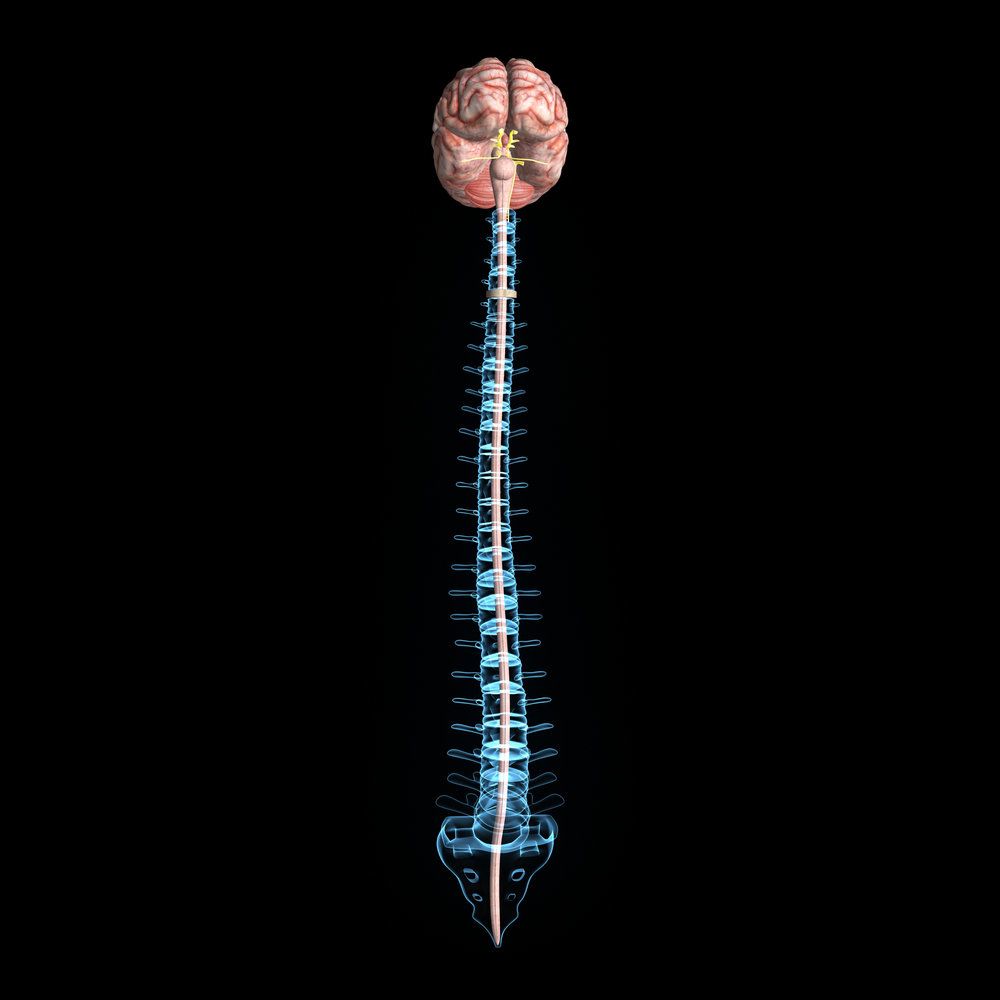

A 24-year-old passenger in an automobile accident sustained a traumatic brain injury and fractured femur. We secured $1.75 million to cover medical bills and more.